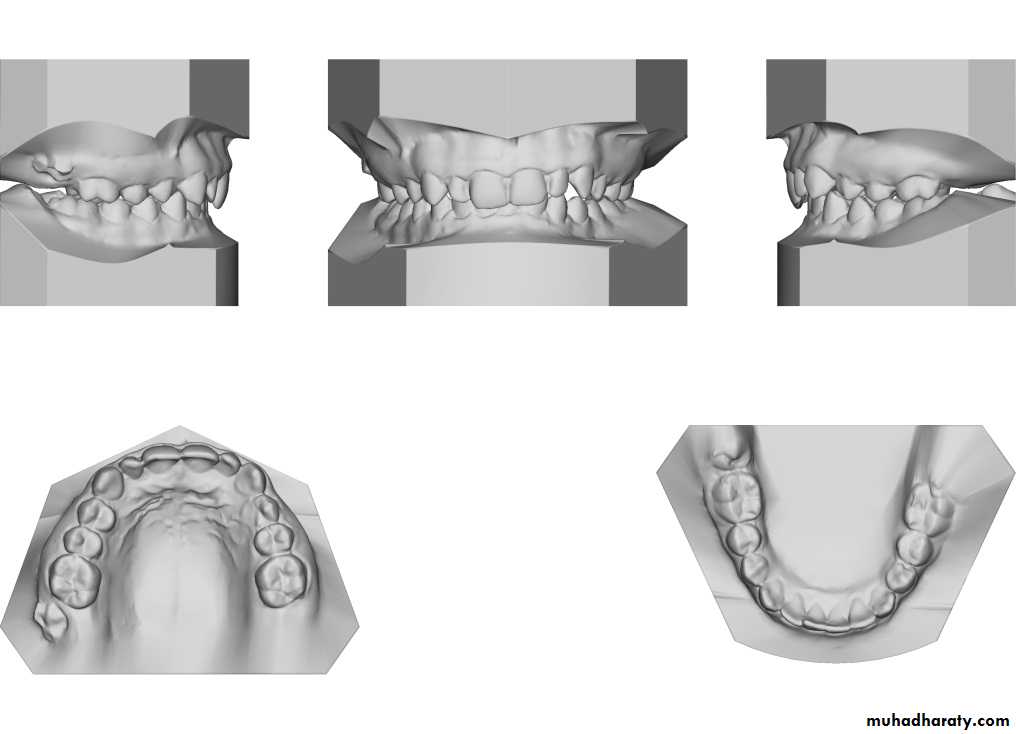

Surgical movement of maxilla and mandible inherently alter the maxillary-mandibular dental occlusion, and as such, careful analysis of the dental models with the orthodontist is essential. The maxillary dental and mandibular dental casts can be studied individually and hand manipulated with each other to assess how the arches are coordinated.Assessment of the models includes space analysis and arch length, transverse width discrepancies, position of the individual tooth within its own arch, and the relationship of the maxillary dentition to the mandibular dentition.

• The surgeon makes osteotomies (ie, incisions) between the teeth in the plaster maxillary cast to create a precise occlusal fit.

• The surgeon then performs the planned surgical procedure on plaster models of the patient’s jaws and teeth and uses these models for reference during the actual surgery.

• The surgeon makes a plastic transitional splint or jig on the model and uses in surgery to position the mandible according to the maxillary position or to position the maxilla based on the position of the mandible

• The jaw may be reshaped on the model until the proper position is obtained.